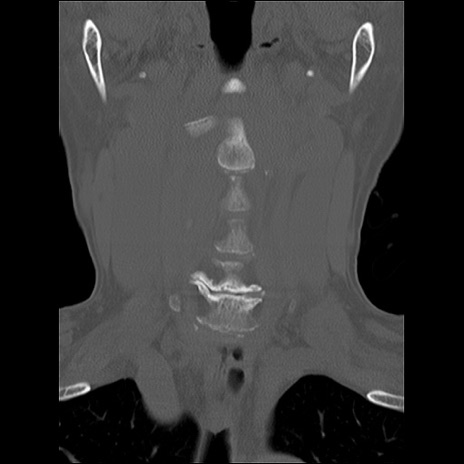

症例48 頚椎CT(冠状断像)

頚椎CT